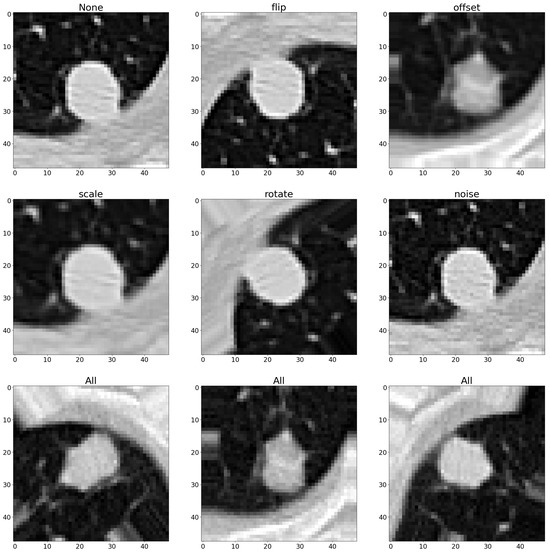

3.4. Augmentation Methods in Lung Nodule Detection

3.4.1. Flipping the Images

3.4.2. Shifting the Image Around

3.4.3. Scaling the Images

3.4.4. Rotating the Images

3.4.5. Injecting Noise into the Images